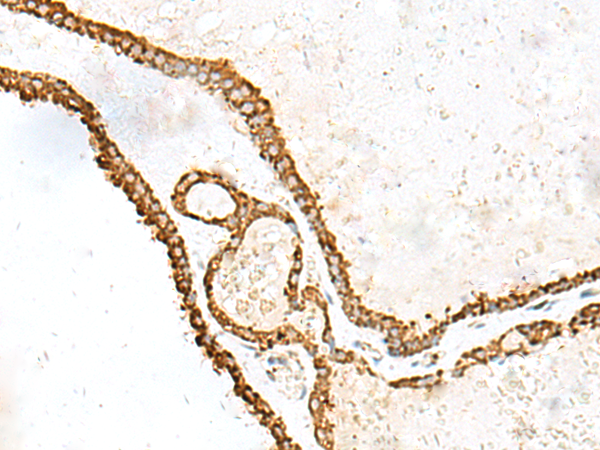

分类: 科研抗体货号: P09929别名:应用: IHC反应种属: Human